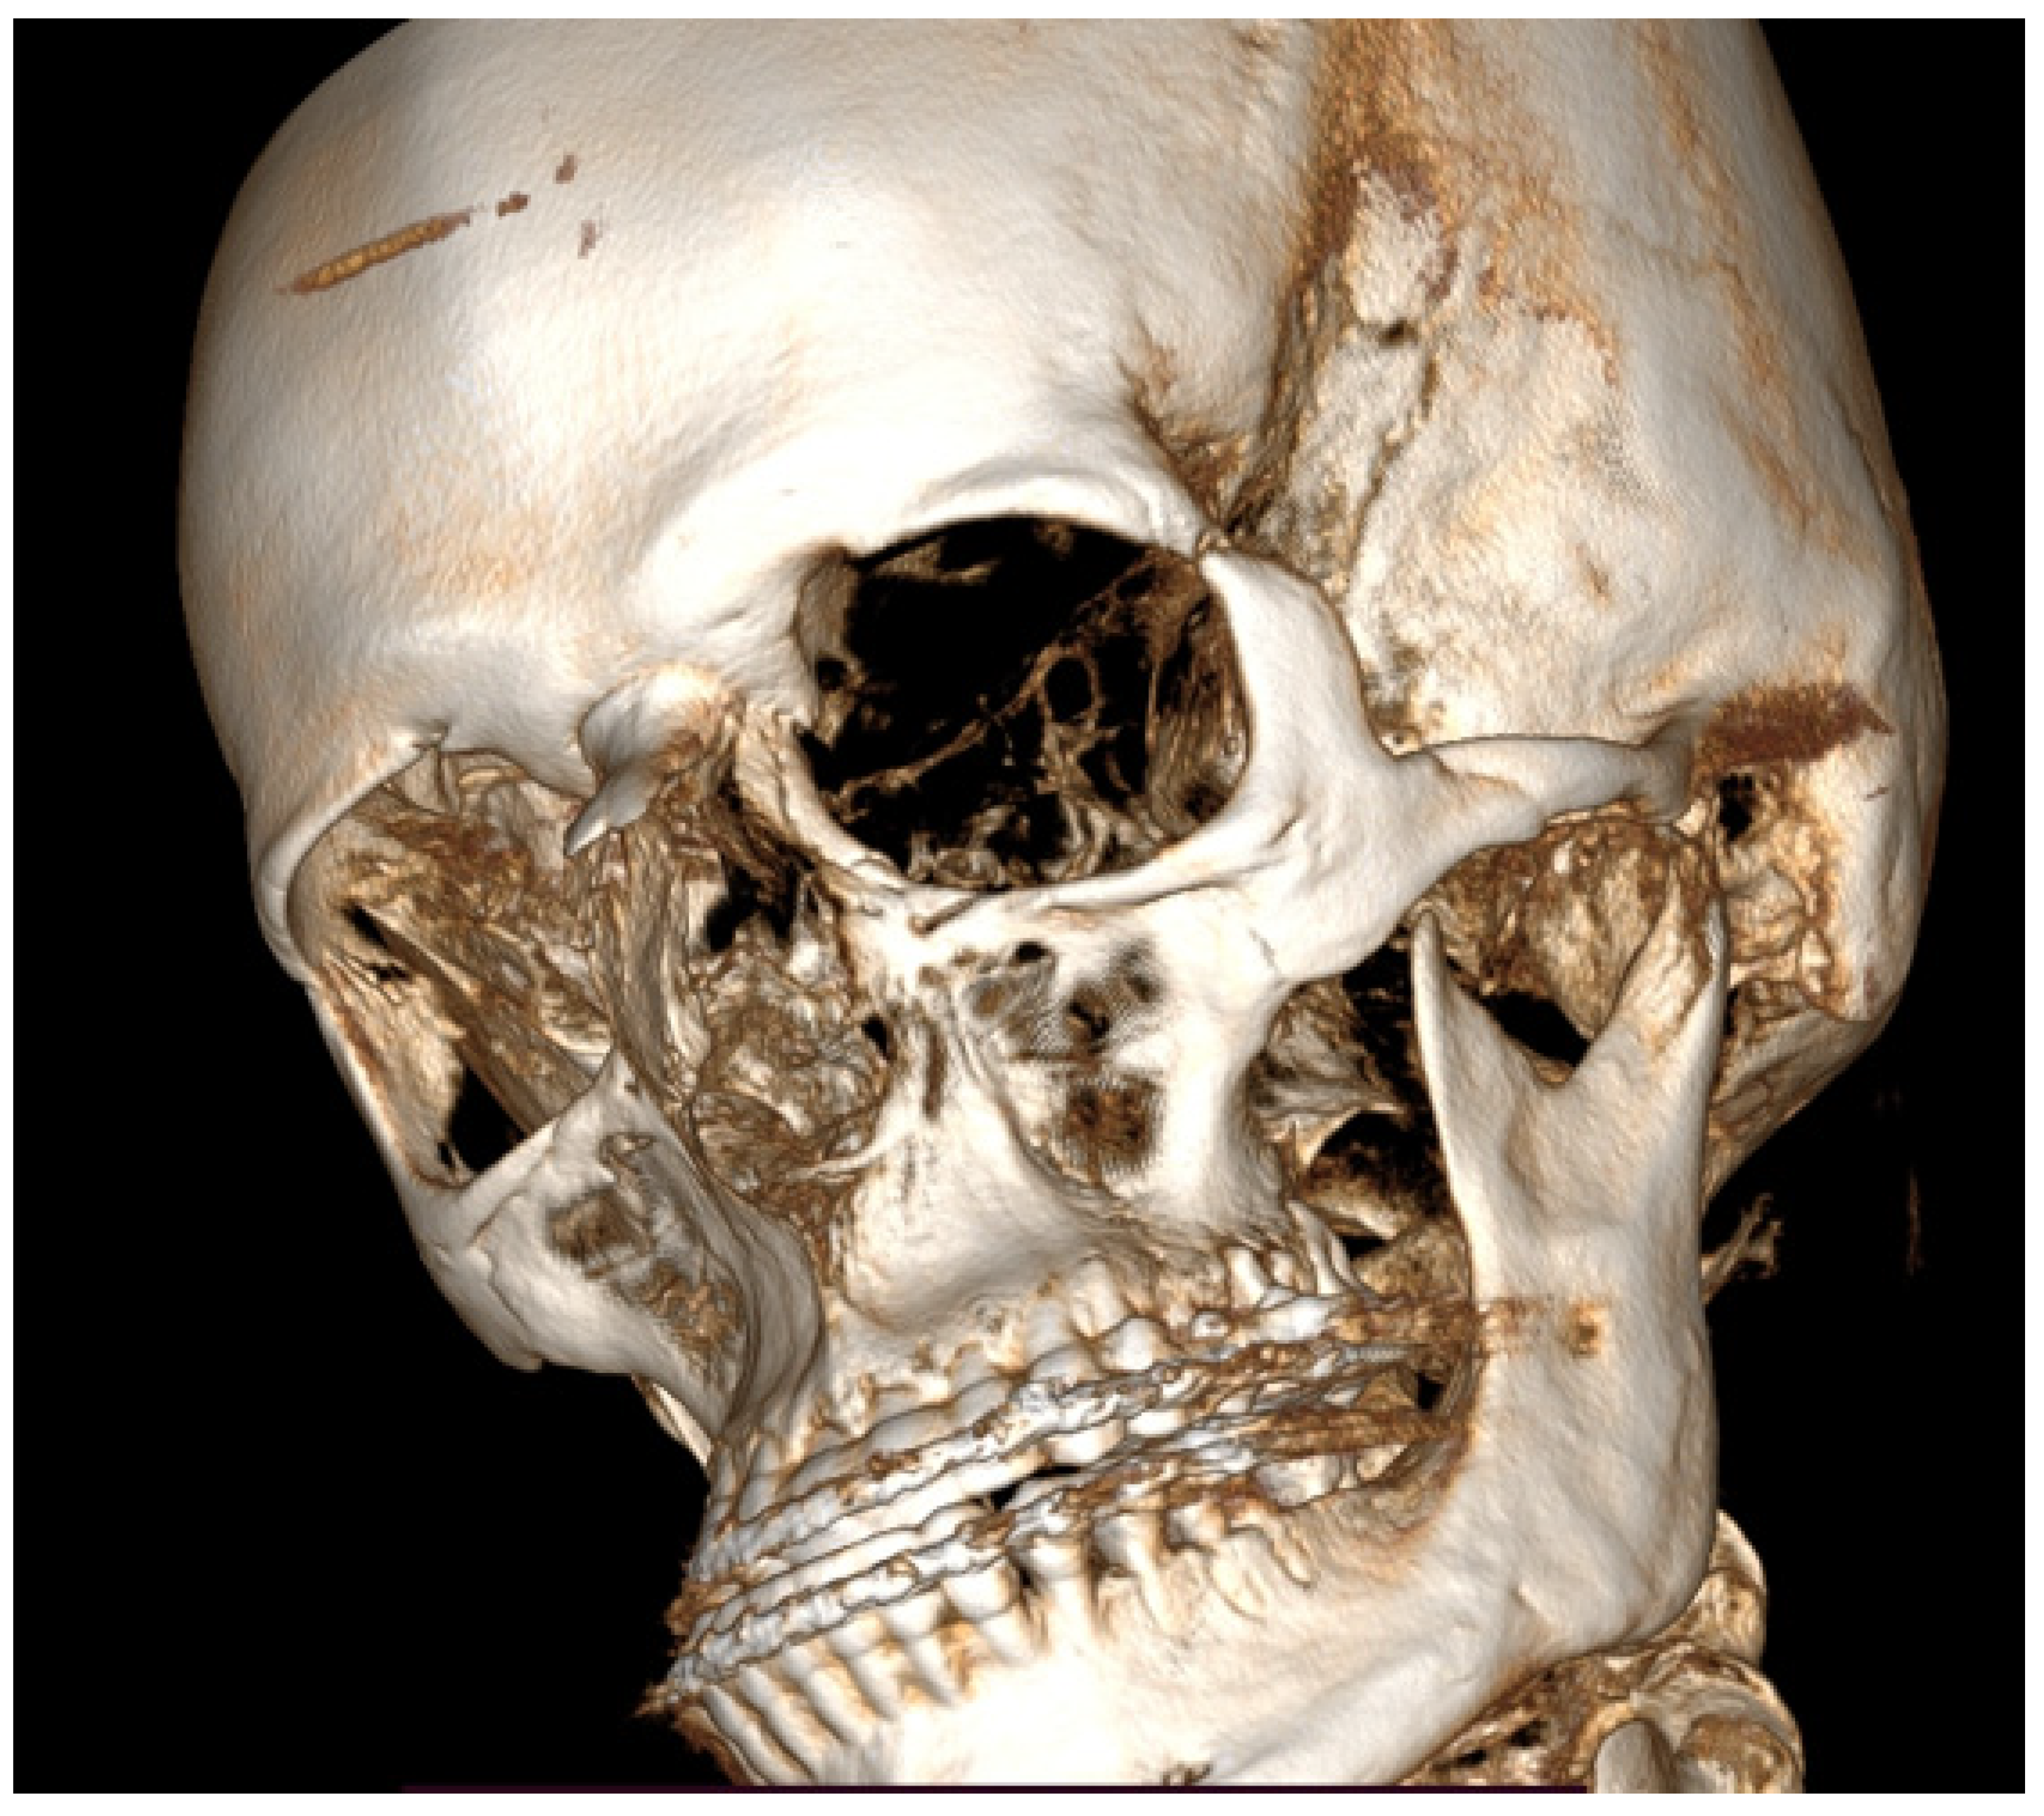

A CBCT-3D reconstruction with visible enlargement and overgrowth of the left mandibular condyle head. Also, a tendency for skeletal class III deformity is visible. In such cases of severe skeletal asymmetries, a necessity for orthognathic surgery procedures is quite important to improve facial symmetry, oval, and contour. The presented images are quite interesting because the unilateral condylar hyperplasia in this case slowly grew over the years and was not found before the first orthognathic procedure in the past; this was the main source of skeletal asymmetry relapse over the next years.